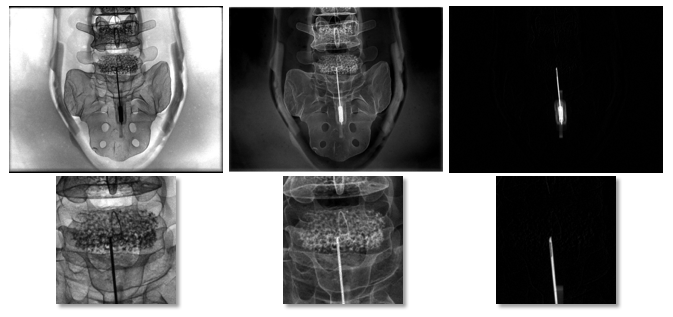

The experimental data for our experiment was collected at Stanford University using a Zeego C-arm device (Siemens Healthineers, Forchheim). Using prototype software, scans of a Sawbones pelvis phantom were acquired. For the three different energy settings, 41, 70, and 125kVP were selected. Image dimensions were pixels. In order to get reference labels for the ground truth, we inserted a biopsy needle into the phantom, performed the three scans, and carefully removed the needle to cause minimal motion of the phantom. Subsequently, another series of three scans was performed. In order to generate the ground truth, the 125 kVp scans before and after needle insertion were subtracted. Examples of the X-ray images are shown in Figure 3.

Figure 4 shows the prediction result visually. The needle is visualised well in all four versions of the material decomposition and the plastic grip is removed. No bone is shown in the image anymore. Still, there are some artefacts in the background of the image that decrease with increasing use of prior knowledge.